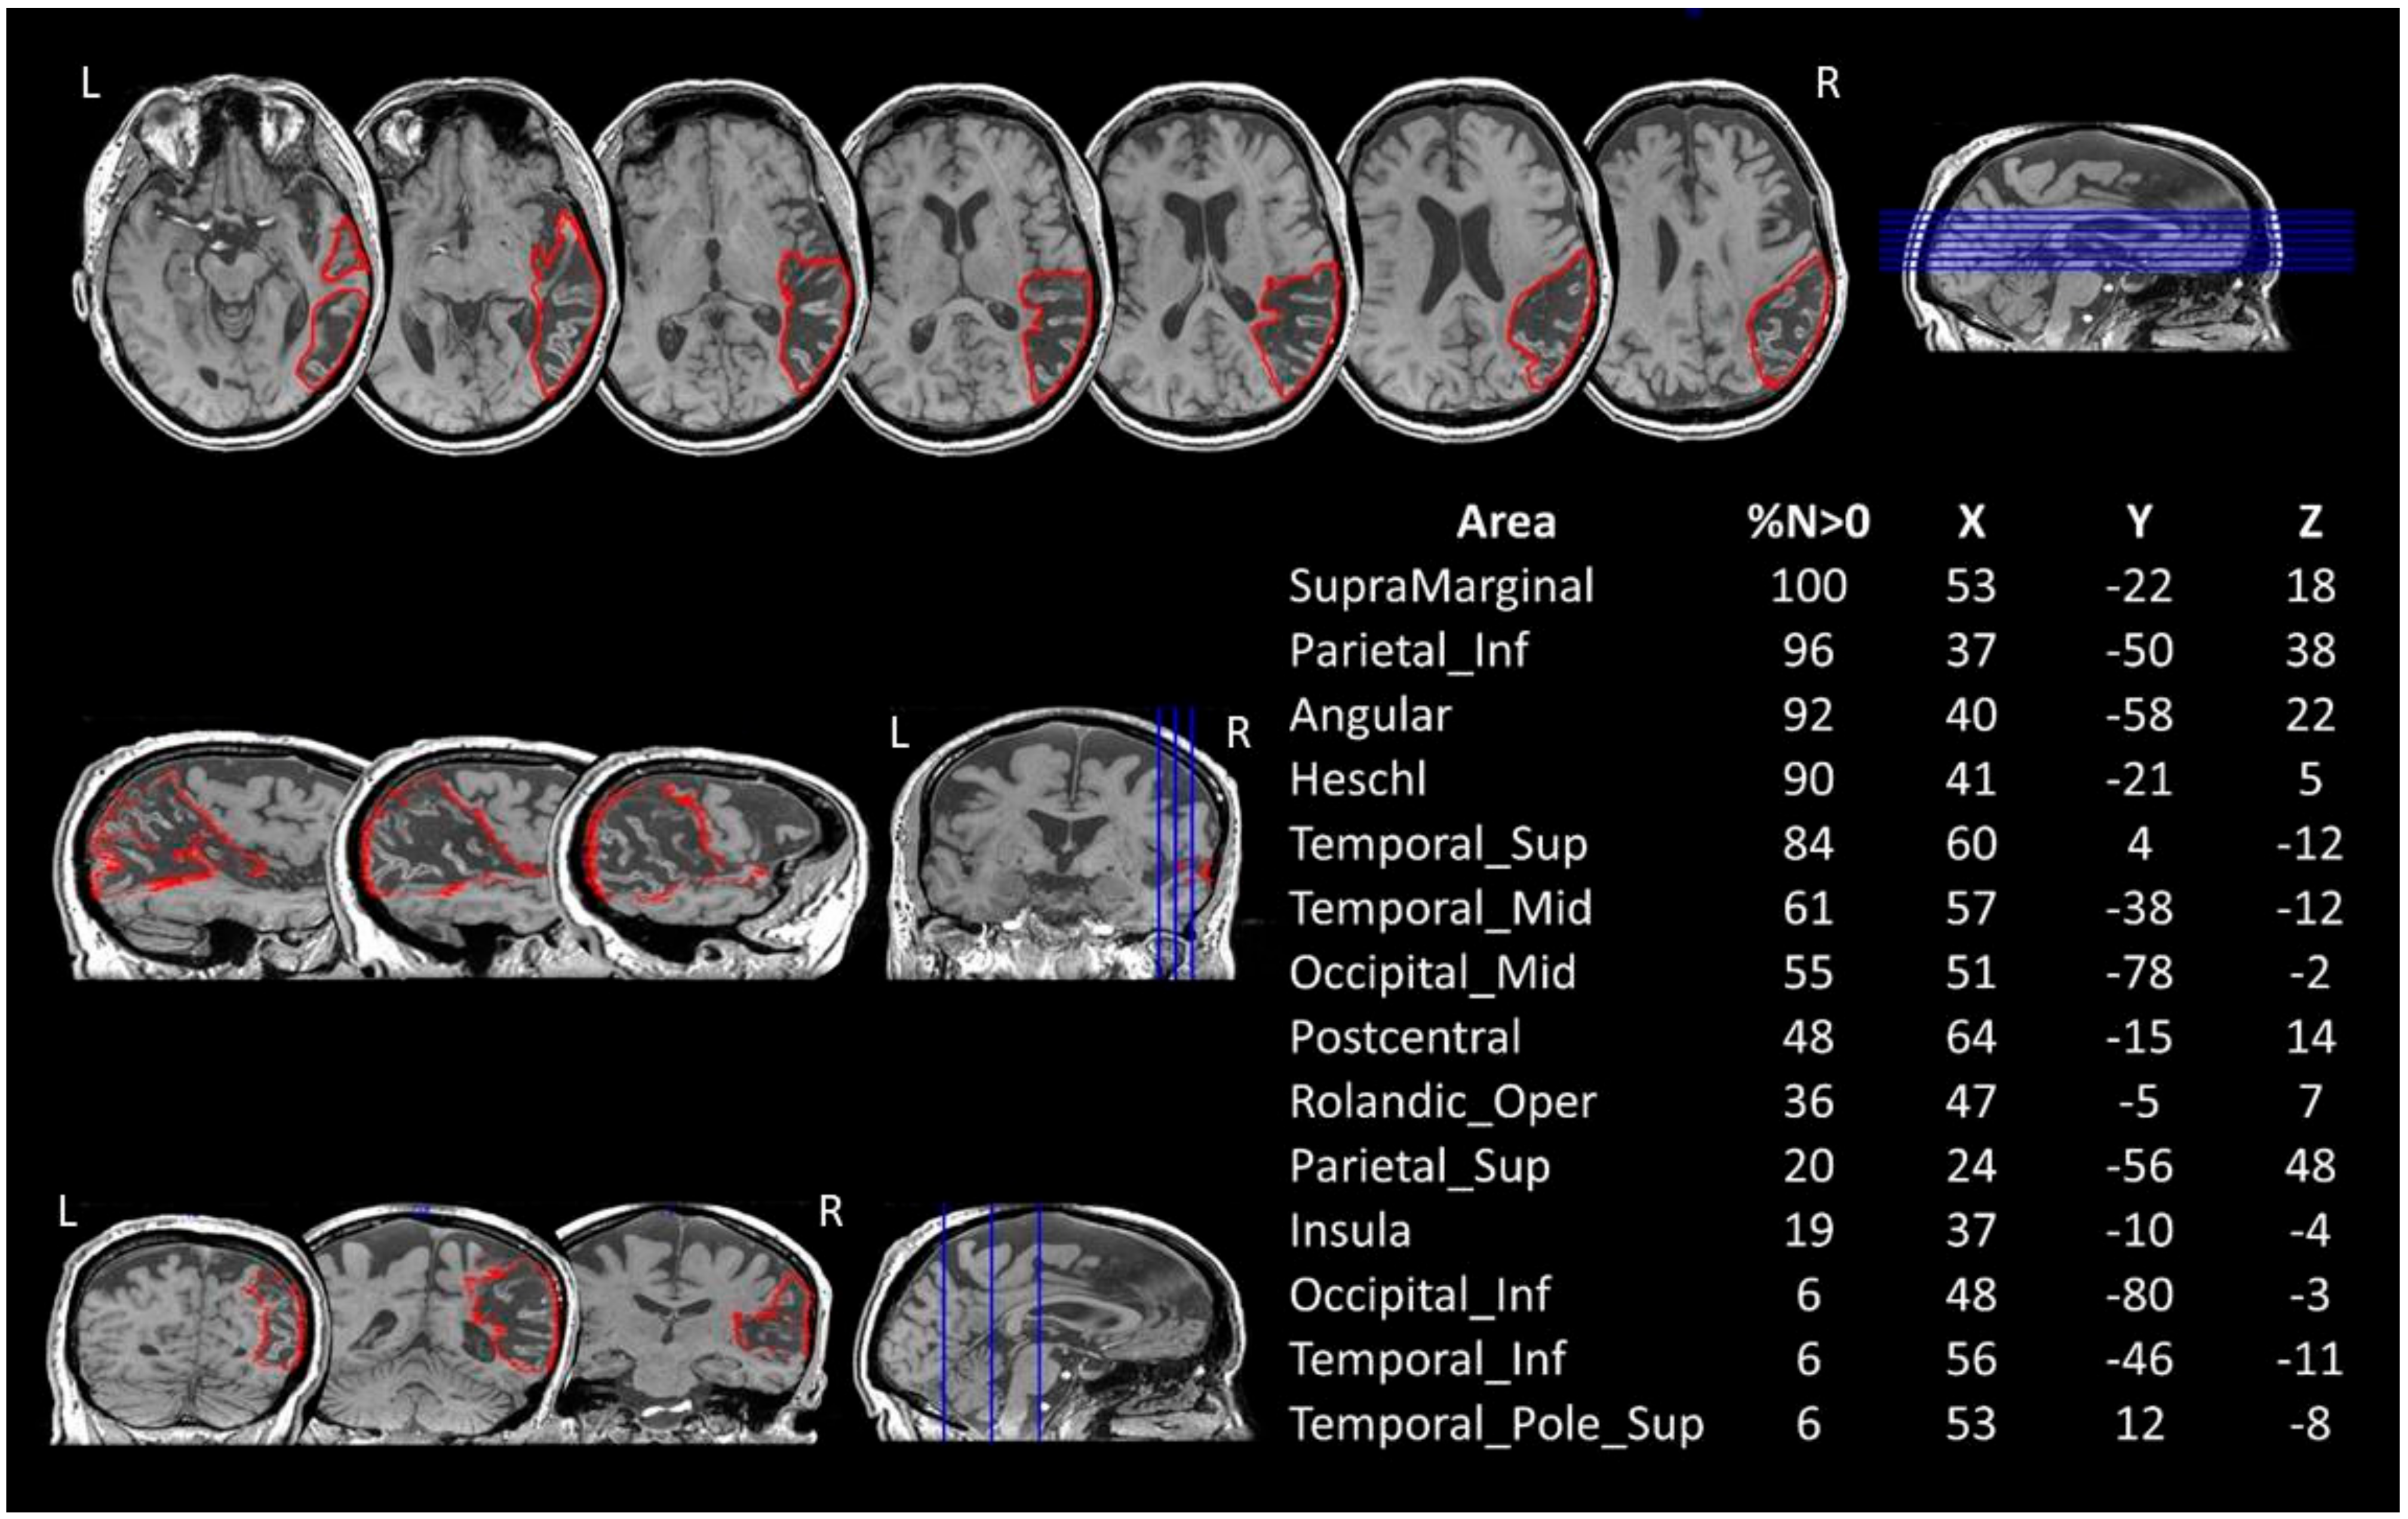

Five months after the stroke, the patient underwent a 3D-T1 and 3D-T2 radiological 3T MRI (Signa Architect, General Electrics, Milwaukee, WI, USA) examination. The lesion analysis was performed using the 3D-T1 MRI image. The lesion was manually drawn on the MRI axial slices and then reconstructed as a 3D region of interest (ROI) with MRIcroN [18]. The MRI scan and the ROI were then spatially normalised to a MNI template by means of SPM8 (Statistical Parametric Mapping; http://www.fil.ion.ucl.ac.uk/~spm, accessed on 6 March 2019).

To identify the grey matter structures encompassed by the lesion, BG’s normalised lesion was then compared with the AAL brain atlas [19] (Figure 1). The damaged white matter tracts were at first explored by means of Tractotron (part of the BCBToolkit; [20]; http://www.bcblab.com.html, accessed on 21 March 2019). The resulting drawing of the patient’s lesion was used as a ROI to track the white matter fibres based on a healthy subjects’ dataset [21], setting a threshold of 50% of overlapping maps for the localisation of the lesions [22,23]. Using this procedure, the severity of a tract disconnection can be established by assessing the proportion of the tract that is damaged. Grey and white matter structures damaged in at least 5% of their voxels were considered as candidates for further DTI analyses [24,25].

The comparison between AP’s lesions and the AAL template is shown in Figure 1.

The patient’s lesion in the right hemisphere extends out from pericentral regions, the insula and the temporal lobe to the inferior parietal and occipital cortices. No direct damage to the frontal cortex was recorded.

Figure 1. BG’s 3D-T1 MRI image and lesion mapping. Axial (up), sagittal (middle-left) and coronal (bottom-left) views are shown with the drawing of the lesion in the right hemisphere in red. The table on the right reports the percentage volume (%N > 0) affected by the lesion and the MNI coordinates (X, Y, Z) for each grey matter structure, as reported on MRIcron (AAL atlas). Lesion’s centre of mass = 140.42 × 84.64 × 97.34. L = left. R = right.